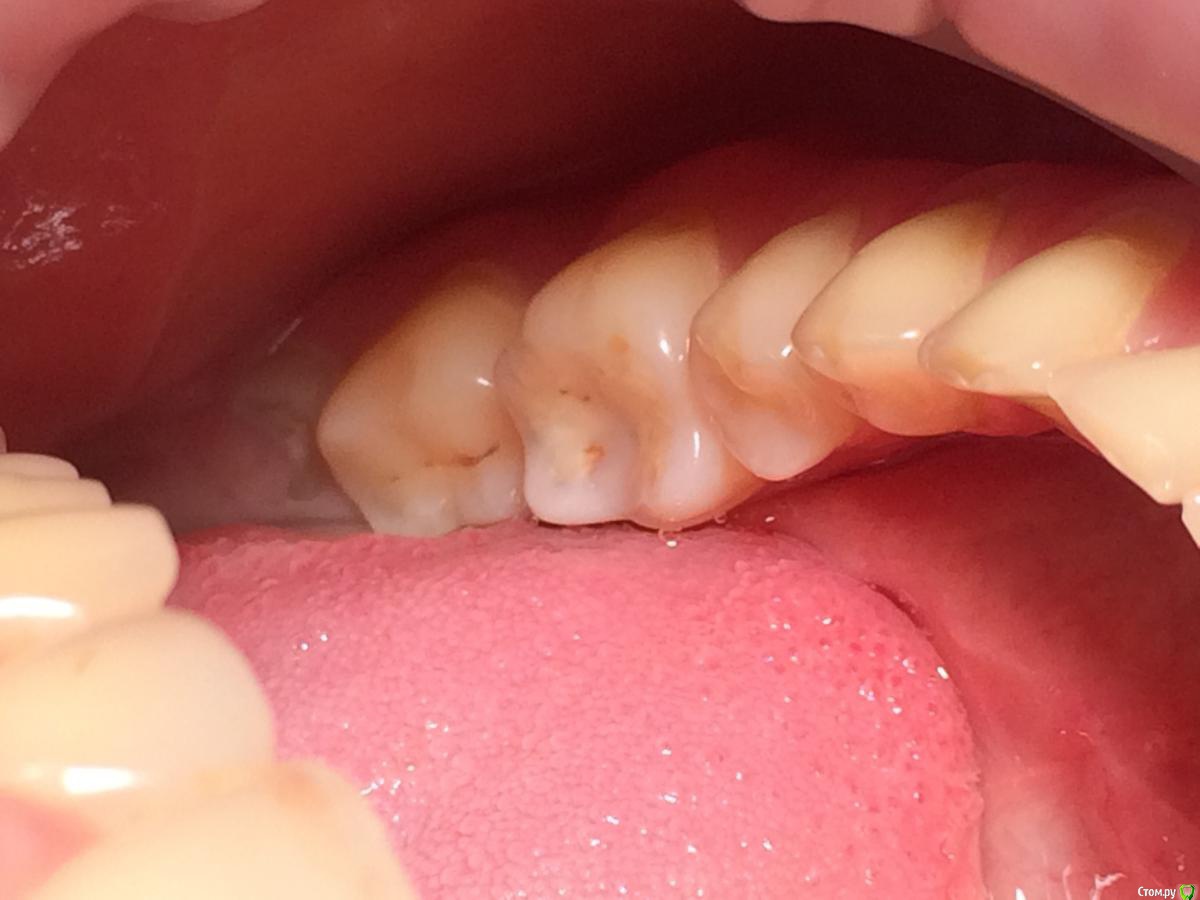

Larnary Опубликовано 28 июля, 2015 Поделиться Опубликовано 28 июля, 2015 (изменено) Добрый день!Ко мне обратилась пациент 1988 гр с жалобой на стираемость зубов и постоянные сколы пломб.Объективно небная поверхность верхних резцов стерта до дентина. Окклюзионная стираемость жевательной группы зубов.Прошу помочь с выявлением причины такой стираемости зубов и оптимальноно метода лечения Изменено 28 июля, 2015 пользователем Larnary Ссылка на комментарий

Larnary Опубликовано 28 июля, 2015 Автор Поделиться Опубликовано 28 июля, 2015 (изменено) Видно окклюзионнык интерференции в области 37 и 47.На днях удален 38 и дальше будут удалены остальные восьмерки. На ТРГ мне видится небольшая ретрузия верхних резцов,дистальный прикус. Так же левпя окклюзионная кривая более выраженная,чем правая Изменено 28 июля, 2015 пользователем Larnary 1 Ссылка на комментарий

Bobby Опубликовано 29 июля, 2015 Поделиться Опубликовано 29 июля, 2015 Фасетки стираемости на нёбных поверхностях верхних резцов и вестибулярных поверхностях нижних резцов обусловлены малым оверджетом - недостаточная щель по саггитали, поэтому и будут колоться реставрации, а ткани зубов истираться. Фрадеани про это на своём курсе рассказывал и показывал видео как это диагносцировать и что с этим делать. Что вообще хочет пациентка и на что готова? Эти вопросы лучше сразу решать на первичной консультации, а то делаете диагностики, всё рассчитываете, распинаетесь, а они потом: "ой, я пока не готов/а к такому плану лечения" и всё заканчивается композитной мазнёй в другой клинике. 5 Ссылка на комментарий